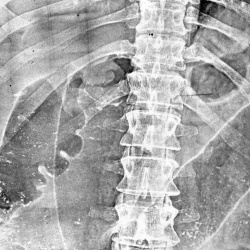

Пациент "взят на контроль" при расшифровке цифровых флюорограмм, дообследован - рентгенография в стандартных проекциях. Ваше мнение коллеги?Произведены томограммы.